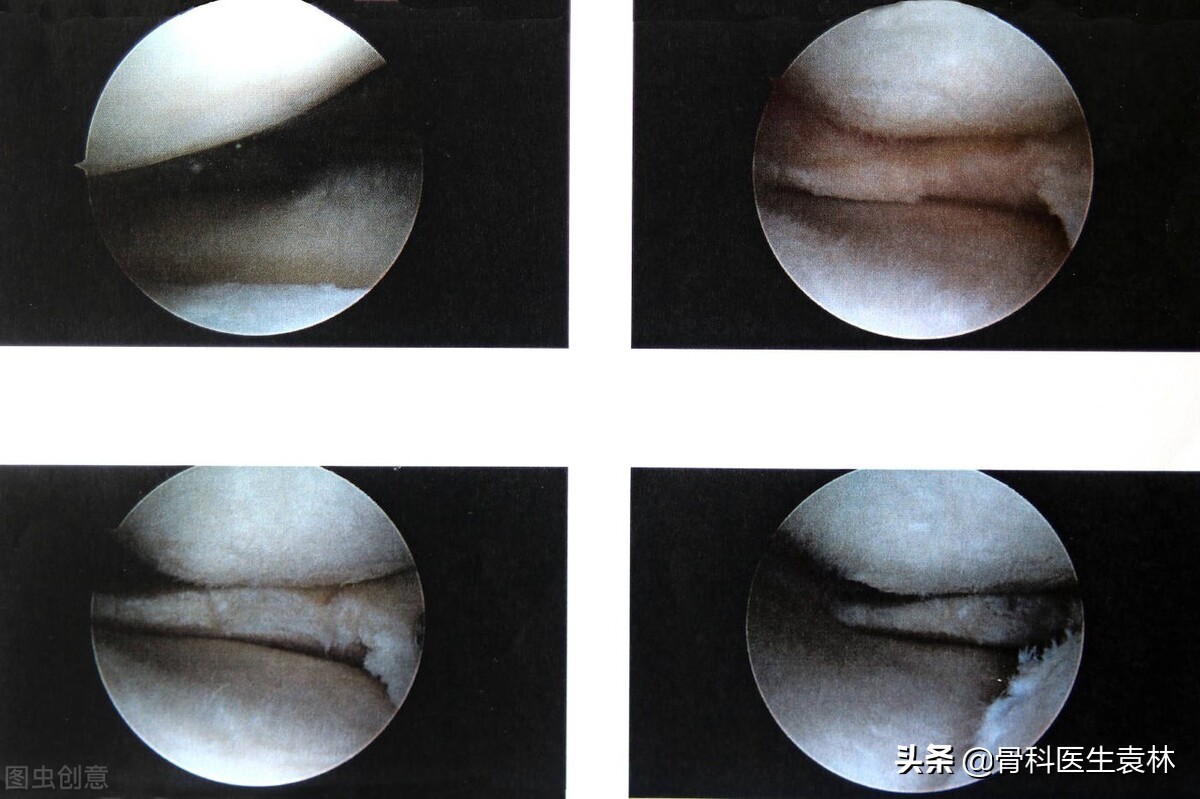

半月板缝合手术后多久可以正常走路?

半月板撕裂手术以后到底需要多长时间的恢复期,才可以下地走路,是与患者采用的手术方式有着最为直接的关系。一般来说分为3种情况。

3、半月板缝合

最后,就是如患者进行的是半月板缝合,为了能够最大程度保证患者的半月板能够愈合,虽然医学上将术后6小时就能下地走路,但这时候患者还不能完全负重运动,需要扶拐杖行走,最好的情况就是佩戴膝关节支具运动。一般情况下,根据患者年龄以及手术的缝合情况,患者可以在4-6周左右的时间之后负重走路,而且支具的佩戴也要在6周左右,基本上3个月后患者就可以从事相关运动了。